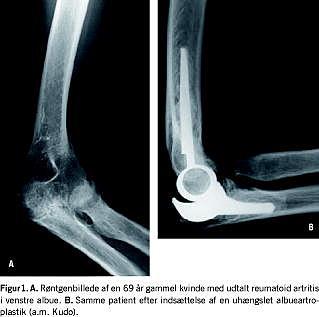

Ved komminutte brud i den distale humerus kan der være indikation for total albueartroplastik, især hos ældre osteoporotiske patienter med intraartikulære brud, hos hvem reposition og osteosyntese ikke er mulig (Figur 2 ) [8-11] og ligeledes kan smerter og bevægeindskrænkning efter sådanne brud være indikation for total albueartroplastik [12]. Der findes et beskedent indikationsområde for total albueartroplastik hos patienter med udtalt instabilitet [13, 14] eller udtalt stivhed af albuen [15] og hos patienter med albuedestruktion pga. hæmofili [16]. Endelig er primær artrose i albuen en sjælden indikation for albueartroplastik [17, 18].